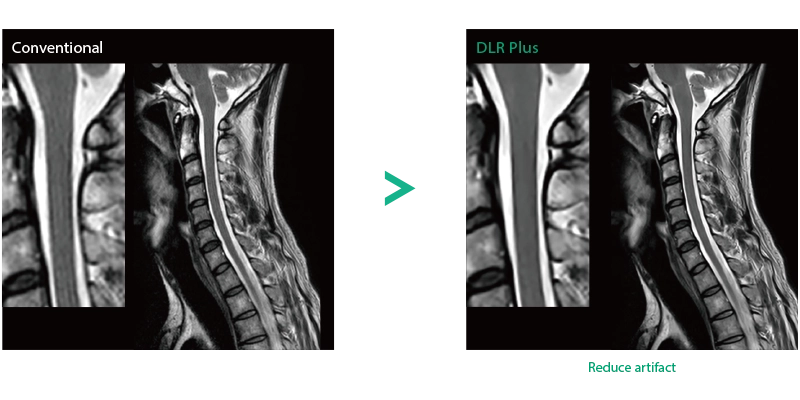

"DLR" is applicable to all body parts and promotes high speed imaging and diagnostic efficiency

IP-RAPID x DLR Plus can also shorten imaging time, allowing more images to be taken in the same examination time.

Additional imaging, such as different image types and cross sections, can be added to the conventional examination to increase the amount of information and make the diagnosis more reliable.

IP-RAPID x DLR Plus gives you the flexibility to shorten respiratory gated series or even replace them with breath-holds, depending on the patient’s situation. This gives you more options and a wider range of examinations to choose from.

IP-RAPID x DLR Plus can be used for basic imaging such as VolumeScan, RadialScan, HalfScan, and many other imaging methods such as MultiContrastScan FatSep and DWI.

It can also be used with time-consuming scans such as Whole Body DWI and Whole Spine imaging, providing more detailed information in many areas than previously possible.

Deep Learning technology*8 enables image quality adjustment after imaging is complete. It optimize SNR and improve image sharpness by processing MRI signals in stages (k-space signal processing). This brings super-resolution and reduces truncation artifacts.